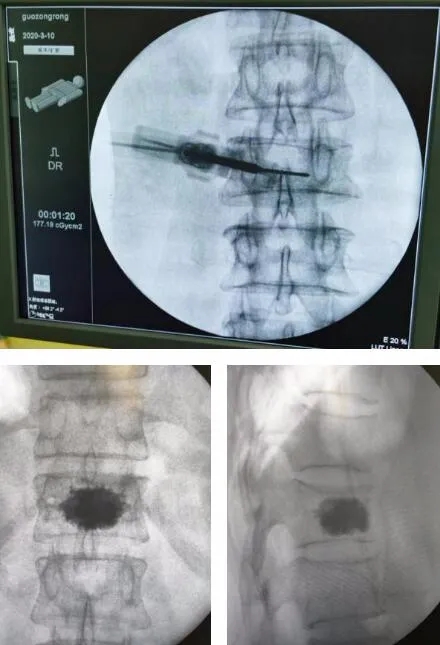

6ÔÂ22ÈÕ£¬£¬£¬£¬£¬ £¬£¬£¬ÃÏ´óÒ¯µÄ×µÌå³ÉÐÎÊÖÊõ¾ÙÐÐ ¡£¡£¡£¡£¡£ÊÖÊõÒ½ÉúÏÈ×°ÖÃ3Dµ¼º½»úеÈËʾ×ÙÆ÷£¬£¬£¬£¬£¬ £¬£¬£¬Í¸ÊÓ¶¨Î»ÐØ12×µÌ壬£¬£¬£¬£¬ £¬£¬£¬ÐÐ3D³ÉÏñ£¬£¬£¬£¬£¬ £¬£¬£¬Ä£ÄâÐØ12×ó²à×µ¹­¸ù´©´Ì£¬£¬£¬£¬£¬ £¬£¬£¬ÔÚ¶¨Î»µã×öÒ»³¤Ô¼0.5ÀåÃ×Çпڣ¬£¬£¬£¬£¬ £¬£¬£¬Í¨¹ýµ¼º½»úеÈËÌ×ͲÓÚÐØ12×ó²à×µ¹­´òÈëµ¼Õ룬£¬£¬£¬£¬ £¬£¬£¬Ö±ÖÁµÖ´ï×µÌåºó1/4´¦£¬£¬£¬£¬£¬ £¬£¬£¬Ìæ»»¹ÇË®ÄàÊÂÇéÌ׹ܣ¬£¬£¬£¬£¬ £¬£¬£¬Í¨¹ýÖÃÈëµÄ¹ÇË®Äà×¢ÈëÆ÷ÔÚ͸ÊÓÏ»ºÂý×¢ÈëÌî³äÔ¼2ml¹ÇË®Ä࣬£¬£¬£¬£¬ £¬£¬£¬´ýÆðÔ´Äý¹ÌºóÔÙ´Î×¢Èë2ml¹ÇË®Ä࣬£¬£¬£¬£¬ £¬£¬£¬È·¶¨×µÌå¸ß¶È»Ö¸´ÇÒÎÞÏÔ׏ÇË®ÄàÍâÒ磬£¬£¬£¬£¬ £¬£¬£¬×îºóÈ¡³ö¹ÇÌî³ä×°Öà ¡£¡£¡£¡£¡£ÊÖÊõ²»µ½1Сʱ˳Ë쿢ʠ¡£¡£¡£¡£¡£